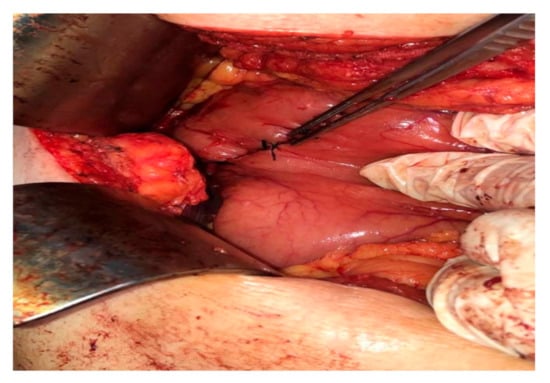

2.4. Operative Findings

3.3. The Intra-Operative Findings

3.4. Gross Findings